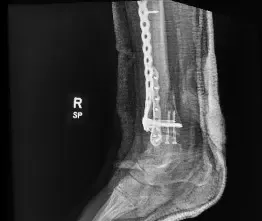

Status post ORIF with plate and screws in the distal fibula and tibia with 2 screws in the medial malleolus. A portion of the fracture line is still evident in the tibia.

Status post ORIF with plate and screws in the distal fibula and distal tibia with healed fracture of the distal shaft of the tibia with mild deformity with anatomic alignment maintained.Healed fracture of the distal fibula without residual deformity.

Healed medial malleolus fracture without deformity.